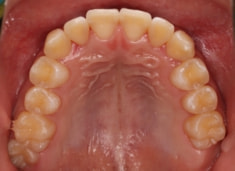

治療前

治療開始時